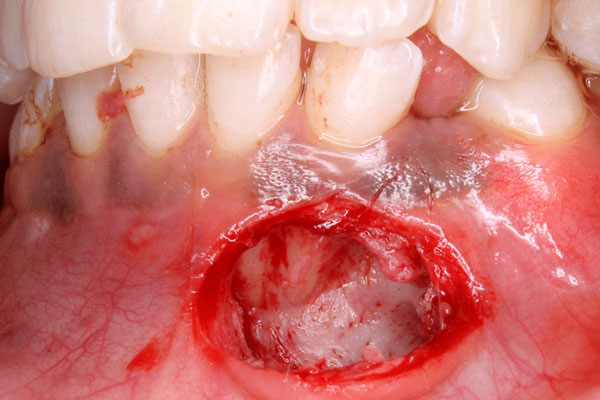

Disimpaction of Impacted canine